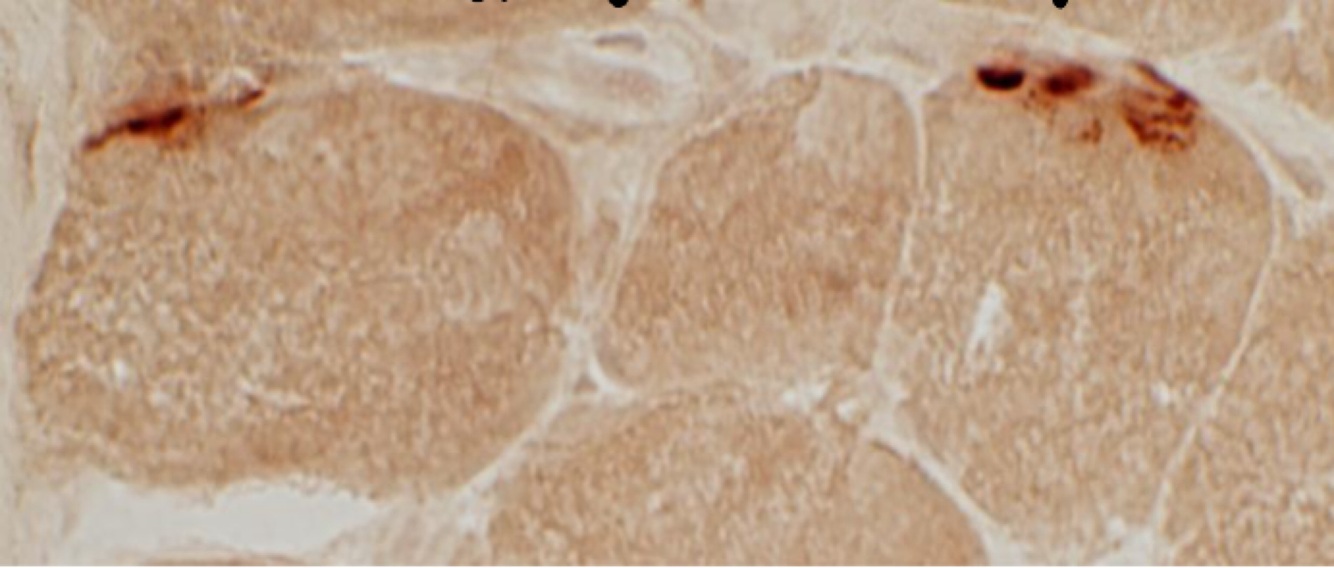

Tissu sain. Les taches foncés représentent les jonctions neuro musculaires